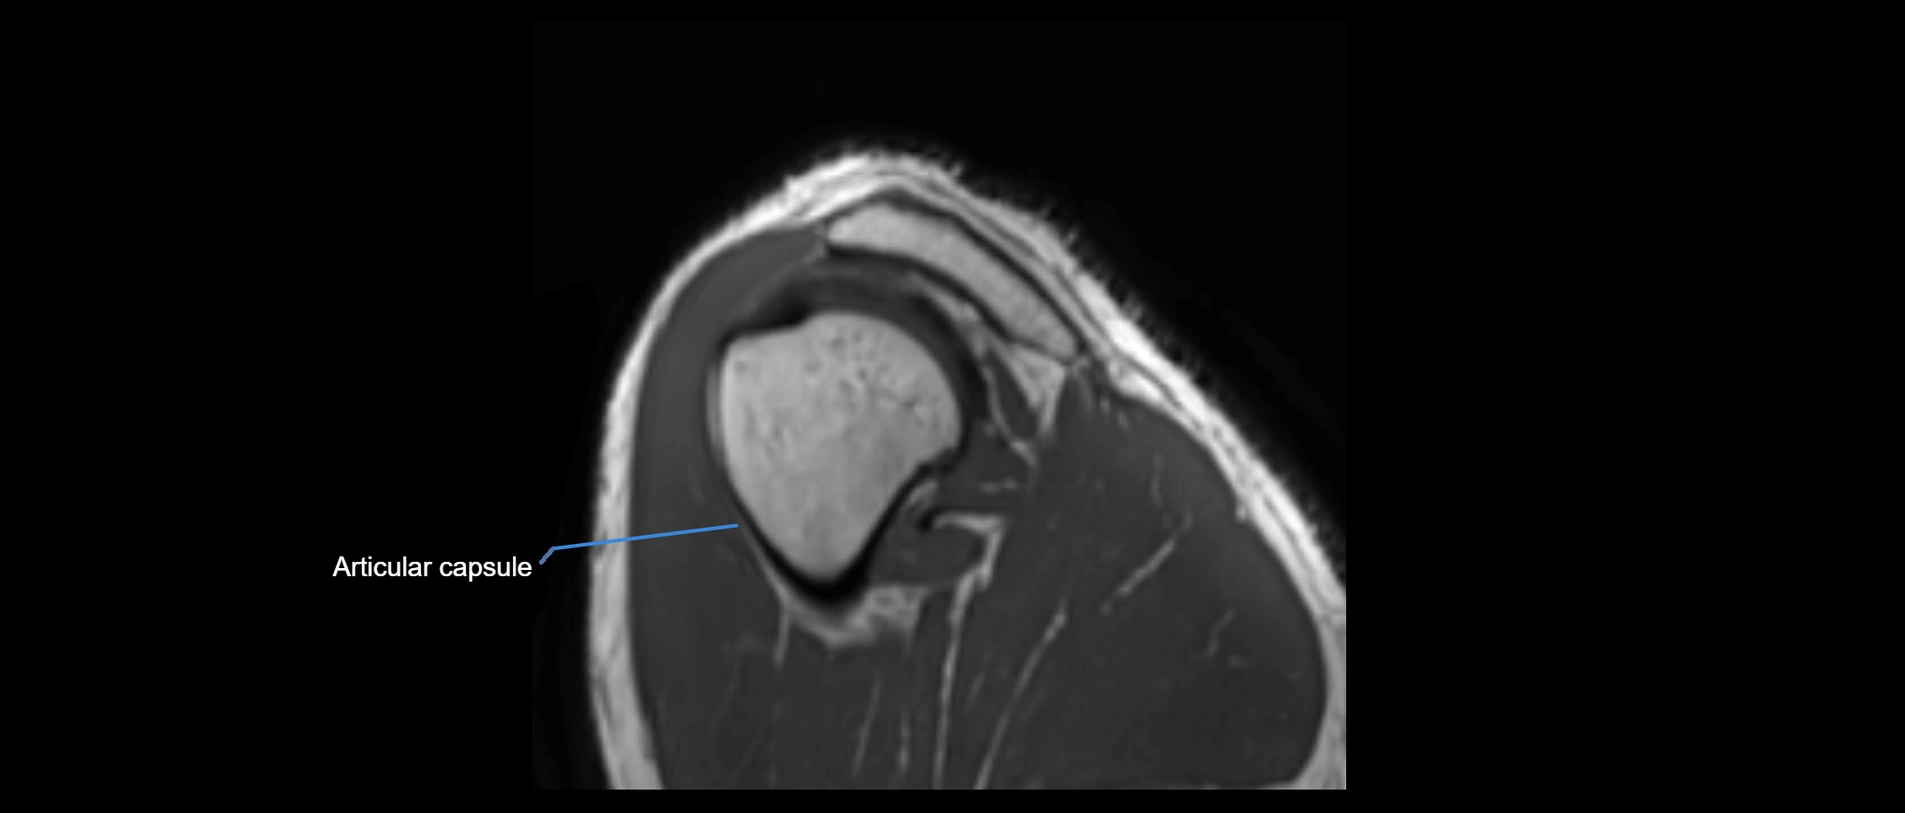

MRI images

image